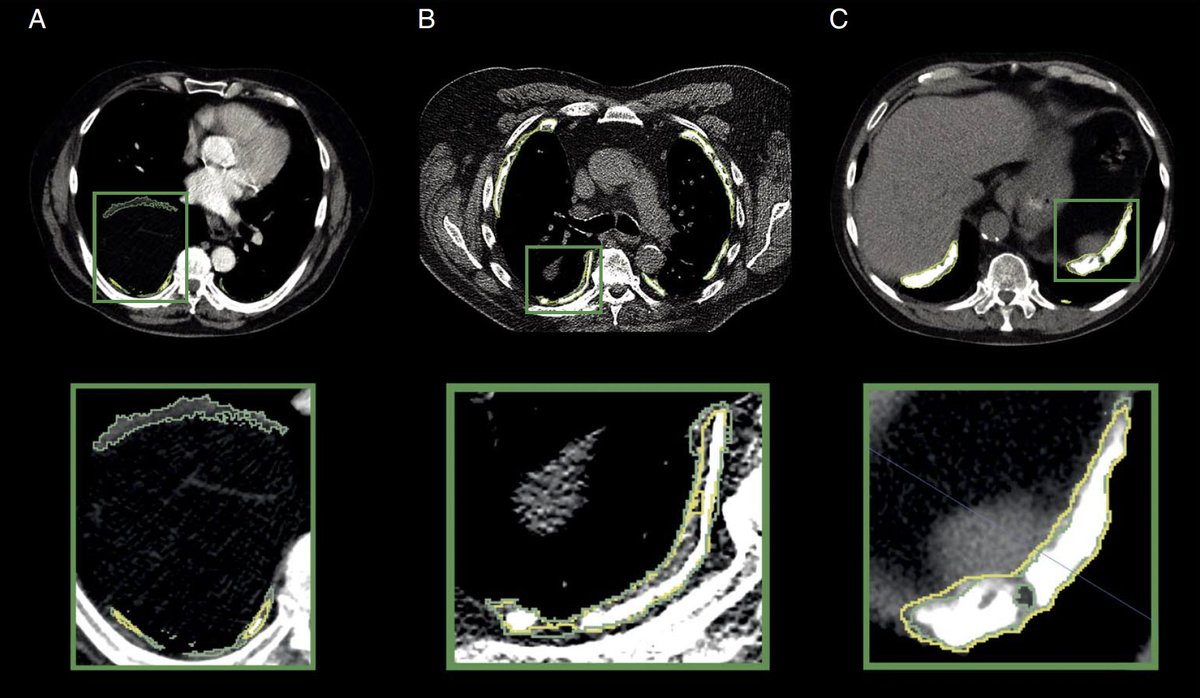

Pleural mesothelioma (PM) grows in a crescent shape along the thoracic wall, complicating diameter-based response evaluation. Manual total tumor volume (TTV) monitoring, while promising, is labor-i...